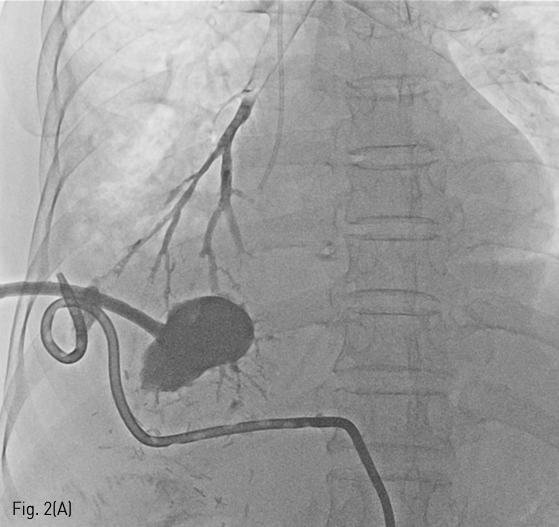

Fig 2A

A radiographic image after injection of contrast via PCD tube to lung abscess, shows direct communication to bronchus of right lower lobe (A).